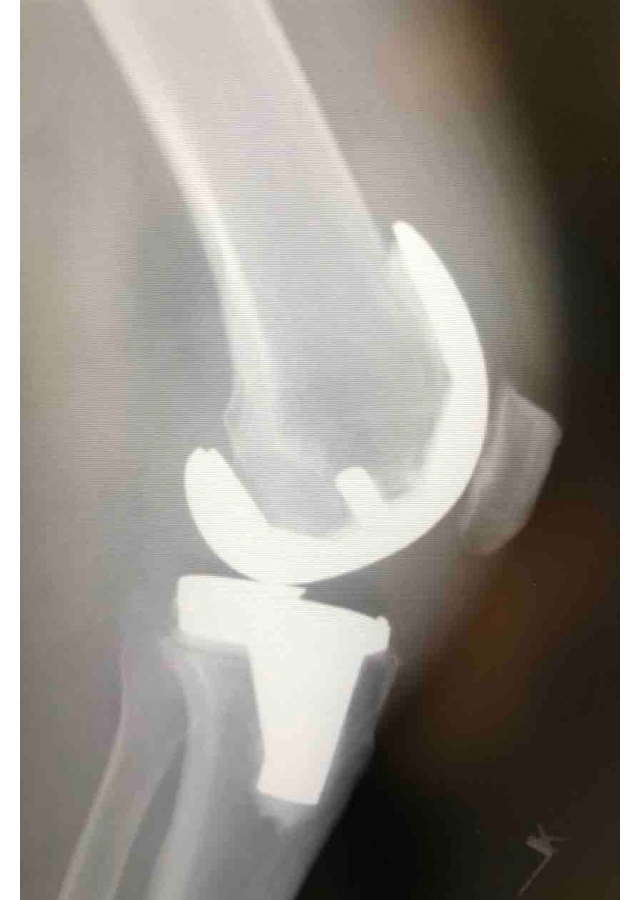

Csípő és térd ízületi betegségek protetizálása

Degeneratívtól, posttraumáson át veleszületett deformitásokig, revíziók, egyszerű és bonyolult helyzetek megoldása.